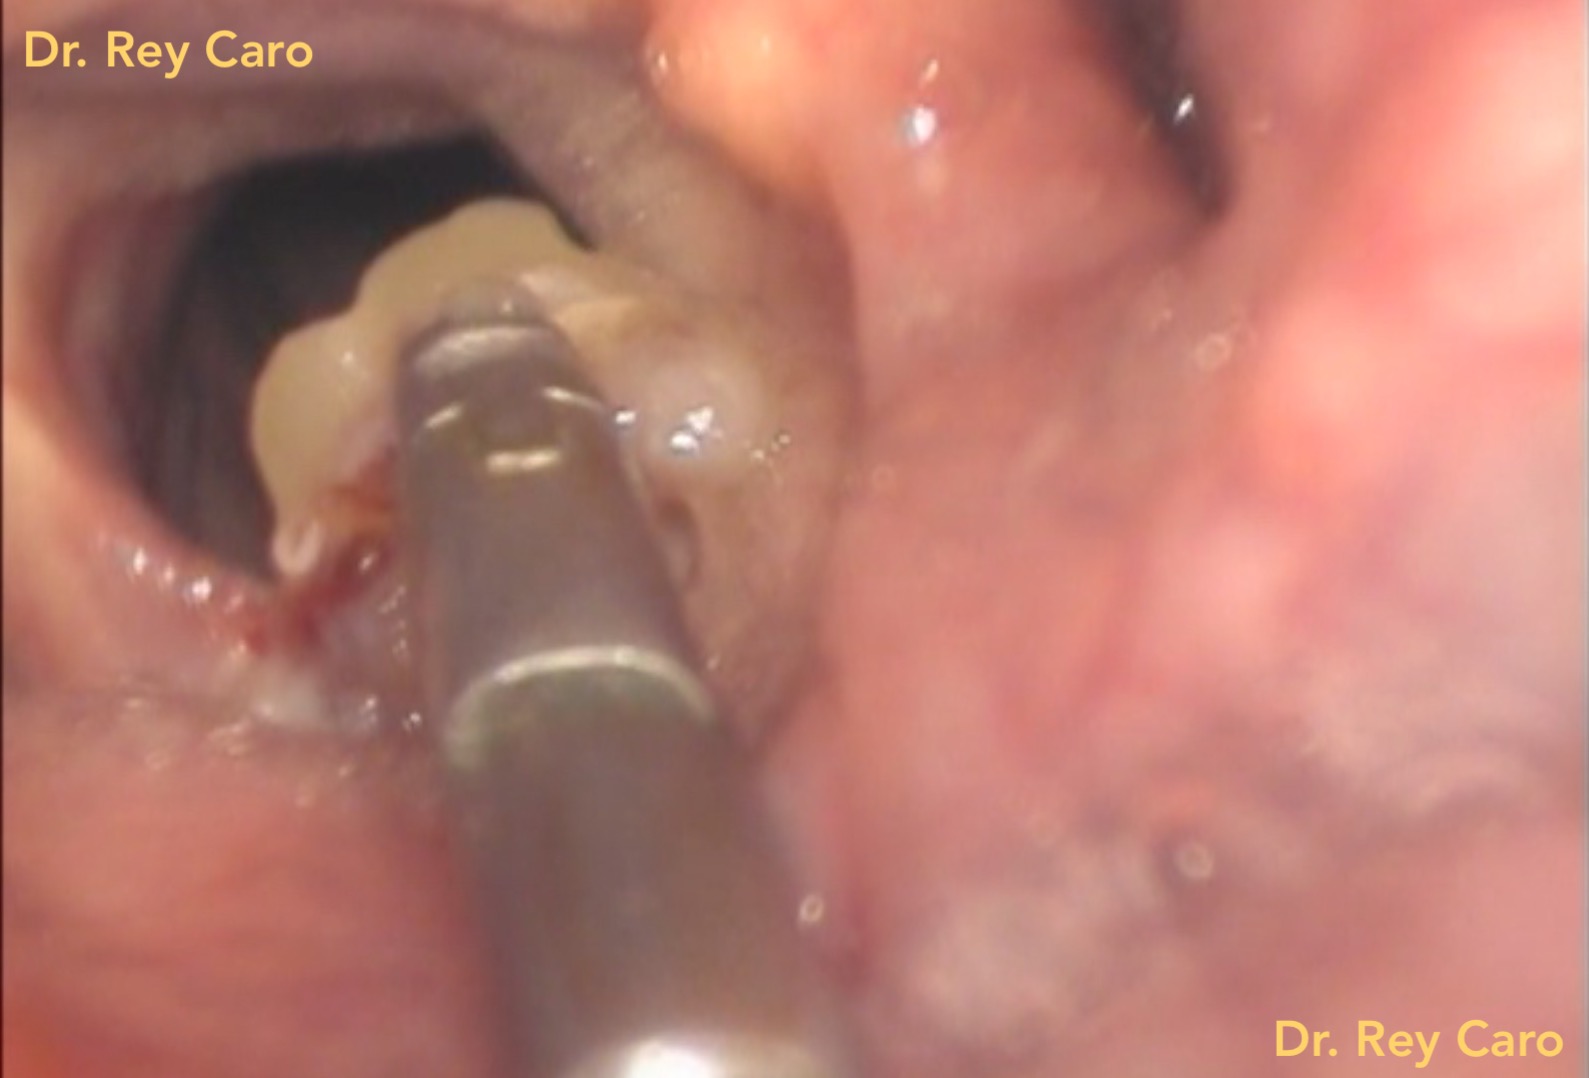

La extirpación de lesiones tipo papilomas (HPV) en cuerdas vocales es posible realizarla en el consultorio bajo anestesia local a través de la boca. Para ello diseñamos, fabricamos y patentamos ante el INPI (Instituto Nacional de Propiedad Industrial, Argentina) el instrumental necesario para hacer posible la cirugía en forma ambulatoria y sin internación. Se utiliza esta técnica generalmente para lesiones pequeñas o recidivas de la enfermedad detectadas tempranamente, con el fin de lograr la curación definitiva de la afección.

Caso 1: papiloma residual en cara superior de ambas cuerdas vocales

Foto: Papilomatosis de laringe: 30 días post extirpación de papilomas por vía oral bajo anestesia local